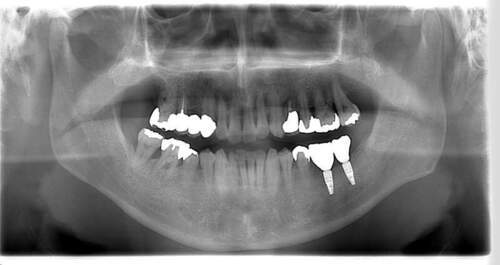

インプラント治療の症例4

レントゲン写真

- Befor

- After

| 治療内容 | 左下6番抜歯、左下6番7番骨造成、インプラント埋入 |

| 治療方針 | 元々支台歯に負荷がかかりやすいとされている延長ブリッジを抜歯し、1本単体でしっかりかめるようにインプラントを2本埋入した。骨吸収も進んでいたため、※GBR法で骨造成を同時に行った。 治療と並行して、全顎的な歯周病治療も行い、今後は歯周病が進行しないよう、こまめにメンテナンスに通っていただく。 |

| 担当者所見 | 6番は歯根分割された被せ物が7番の欠損部との延長ブリッジとされており、強い咬合と歯周病も相まって負荷がかかり動揺し、歯として機能しなくなったため、抜歯となった。 |